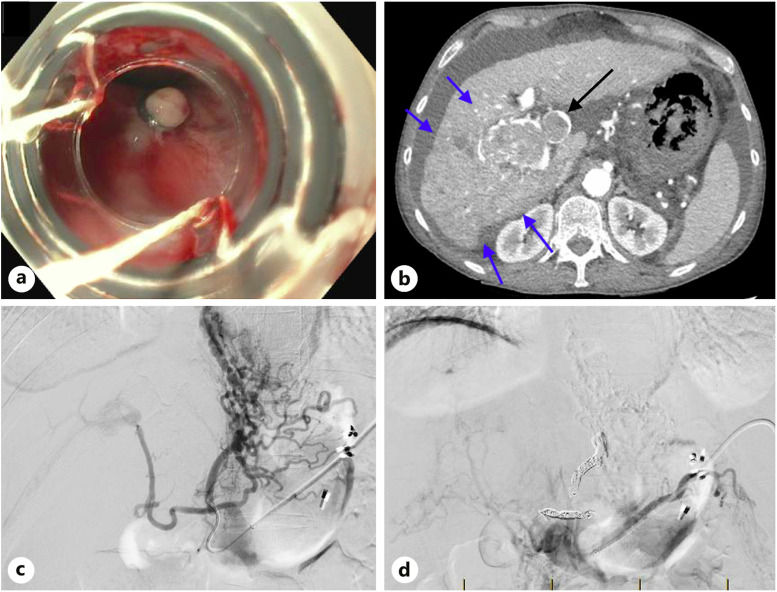

Case presentation: We report a case of a 61-year-old male newly diagnosed with hepatocellular carcinoma and extensive portal vein thrombosis. The patient developed a refractory EVB failing medical and endoscopic therapies which was successfully treated with transcutaneous left gastric vein embolization (LGVE).

Conclusion: LGVE could be contemplated in instances where anatomical complexities or contraindications to TIPSS arise.